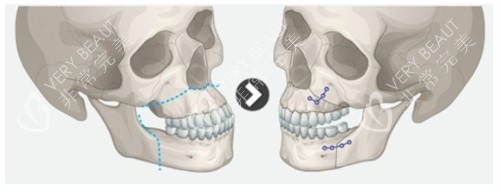

朋友小琪也在另一家医院做过轮廓手术,她说:你这种咬合问题得找能做正颌的医生,普通磨骨解决不了根本。罗医生的方案里,除了调整骨头位置,还详细标注了颏成型的衔接设计,说要避免阶梯感,这点让我特别安心。

手术当天早8点进准备室,护士给我戴头套时轻声说:罗主管今天推了其他手术,专门给你做。进手术室看到罗医生在调试四维头影测量仪,电脑屏幕上是我术前拍的CT重建图,他指着下颌角位置说:等会这里截3mm,那边2.5mm,对称度能控制在0.5mm内。麻醉师让我深呼吸时,我突然闻到罗医生白大褂上淡淡的消毒水味——和我爸当外科医生时的味道好像,莫名就踏实了。

很多人问我双颚手术疼不疼风险大不大,我想说:疼痛是暂时的,自卑才是一辈子的。但一定要选能做正颌的医生——罗医生做过1000+台颌面手术,连截骨角度都更好到度,这才是富有经验的底气。我术前特意查了他的执业证书,是口腔颌面外科副主管医师,和普通整形医生的资质完全不一样。